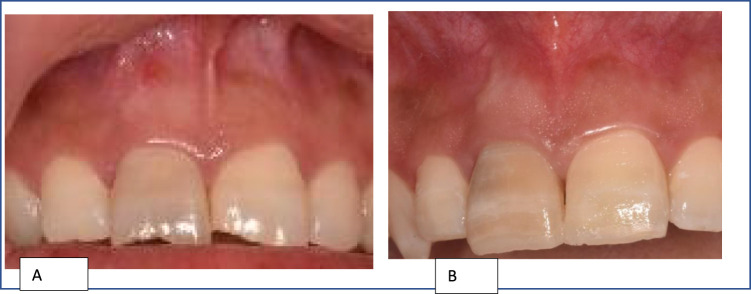

This case report details a pulp revascularization treatment administered to a mature permanent tooth exhibiting pulp necrosis. A 22-years old female patient complained of the recurrence of a sinus tract labial of the maxillary right central incisor; which was tender on biting. Diagnosis of pulp necrosis and symptomatic apical periodontitis. Preoperative periapical and CBCT radiographs showed root with wide apical foramen and large apical radiolucency. Pulp revascularization procedure was performed using 1.3% sodium hypochlorite irrigation, 17% Ethylenediaminetetraacetic acid irrigation, and calcium hydroxide intracanal dressing for 2 weeks. During the last visit, intentional bleeding was induced, collagen matrix was set over the blood clot, 2 mm of mineral trioxide aggregate and glass-ionomer filling was placed. A year of follow-up, the tooth showed no signs or symptoms and responded normally to the sensibility tests. Intra-oral periapical radiograph and the CBCT showed significant reduction in the periapical lesion's size, slight reduction in the apical foramen's size, and hard radiopaque material deposition at the root's middle third.